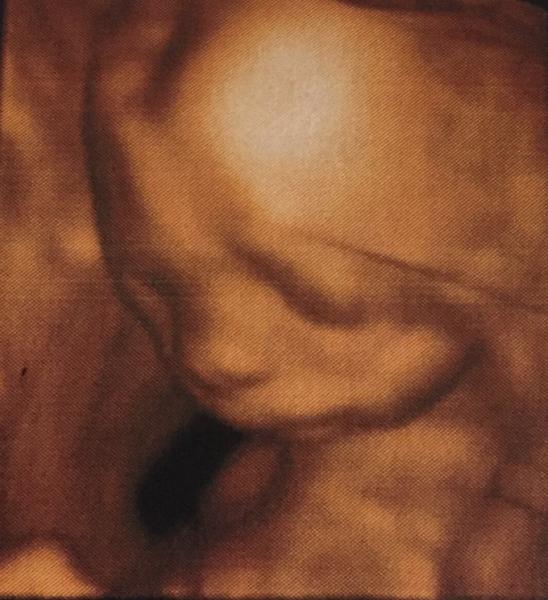

Hallo ihr lieben. Ich hatte ja gestern Feindiagnostic. Es ist alles okay mit der Maus. Die Versorgung passt auch. Die kleine wiegt ca. 340 Gramm und ist in etwas 27 cm groß. Wahnsinn Mittlerweile spüre ich sie auch täglich. Anbei mal noch ein Bildchen. Sie war etwas schüchtern und hat sich in die Gebärmutter gekuschelt

Bild zu Feindiagnostic - Forum für Januar - Mamis